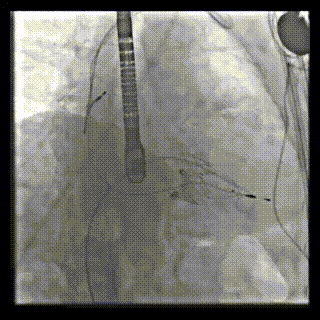

本周三例接受LuX-Valve Plus經(jīng)血管三尖瓣置換術(shù)的患者中,第一例患者為冠狀動(dòng)脈旁路移植術(shù)+Bentall+二尖瓣成形術(shù)后;第二例患者為永久起搏器植入術(shù)后,存在跨三尖瓣導(dǎo)線;第三例患者合并房顫、房缺及左心耳封堵術(shù)后。

三例患者入院后,葛均波院士團(tuán)隊(duì)周達(dá)新教授、潘文志教授、張?jiān)床┦俊㈥惿┦考靶某业呐舜湔浣淌凇⒗顐ソ淌趯?duì)患者的情況進(jìn)行詳細(xì)評(píng)估和討論,最終決定為三例患者選擇LuX-Valve Plus40mm、50mm和50mm型號(hào)的瓣膜進(jìn)行手術(shù)治療。手術(shù)后即刻拔除氣管插管,術(shù)后患者三尖瓣反流癥狀得到顯著改善,復(fù)查心超結(jié)果顯示人工三尖瓣瓣膜支架固定穩(wěn)定,瓣葉關(guān)閉形態(tài)未見異常,未見明顯反流。